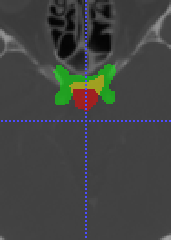

In Chapter 6, we propose an end-to-end, atlas-free 3D convolutional deep learning framework for fast and fully automated whole-volume HaN anatomy segmentation [115]. Our deep learning model, called AnatomyNet, segments OARs from head and neck CT images in an end-to-end fashion, receiving whole-volume HaN CT images as input and generating masks of all OARs of interest in one shot. AnatomyNet is built upon the popular 3D U-net architecture, but extends it in three important ways: 1) a new encoding scheme to allow auto-segmentation on whole-volume CT images instead of local patches or subsets of slices, 2) incorporating 3D squeeze-and-excitation residual blocks in encoding layers for better feature representation, and 3) a new loss function combining Dice scores and focal loss to facilitate the training of the neural model. These features are designed to address two main challenges in deep-learning-based HaN segmentation: a) segmenting small anatomies (i.e., optic chiasm and optic nerves) occupying only a few slices, and b) training with inconsistent data annotations with missing ground truth for some anatomical structures. We collect 261 HaN CT images to train AnatomyNet, and use MICCAI Head and Neck Auto Segmentation Challenge 2015 as a benchmark dataset to evaluate the performance of AnatomyNet. The objective is to segment nine anatomies: brain stem, chiasm, mandible, optic nerve left, optic nerve right, parotid gland left, parotid gland right, submandibular gland left, and submandibular gland right. Compared to previous state-of-the-art results from the MICCAI 2015 competition, AnatomyNet increases Dice similarity coefficient by 3.3% on average. AnatomyNet takes about 0.12 seconds to fully segment a head and neck CT image of dimension , significantly faster than previous methods. In addition, the model is able to process whole-volume CT images and delineate all OARs in one pass, requiring little pre- or post-processing. We demonstrate that our proposed model can improve segmentation accuracy and simplify the auto-segmentation pipeline. These contributions are released as an open-source software package called AnatomyNet, which is publicly available555https://github.com/wentaozhu/AnatomyNet-for-anatomical-segmentation. Portions of this chapter were published as part of [115].

- [121] W. Zhu and X. Xie. Adversarial deep structural networks for mammographic mass segmentation. arXiv:1612.05970, 2016.